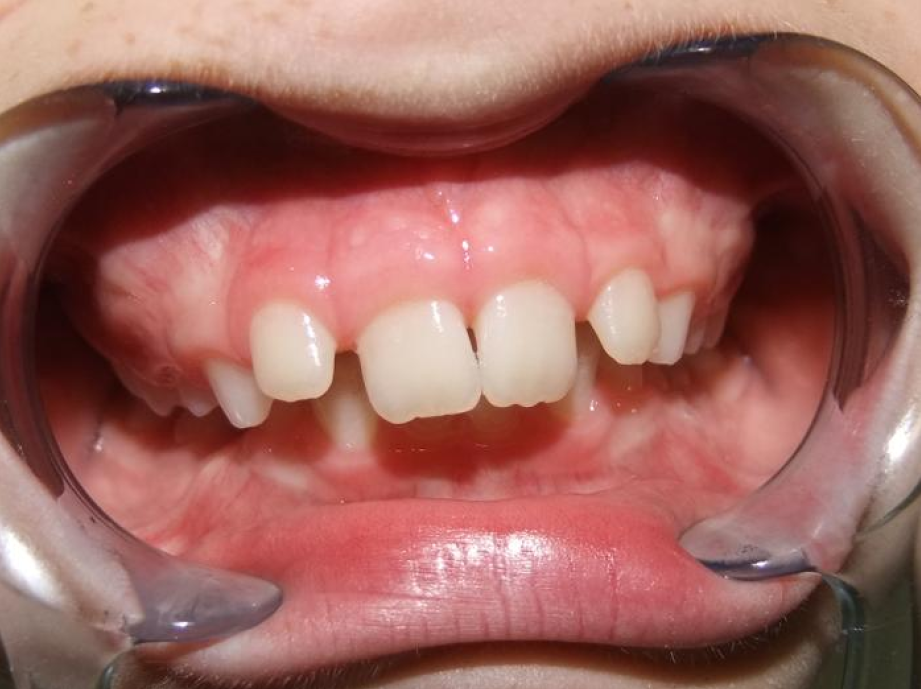

eindfoto

Leeftijd bij aanvang: 9 jaar

1-6 Bonded Hyrax + partieel vast onderkaak + TransForce onderkaak

7-13 Twinblock

13-22 volledig vast onder- en bovenkaak + rotator

Retentie: wrap en c-c bar

Leeftijd bij retentie: 12 jaar